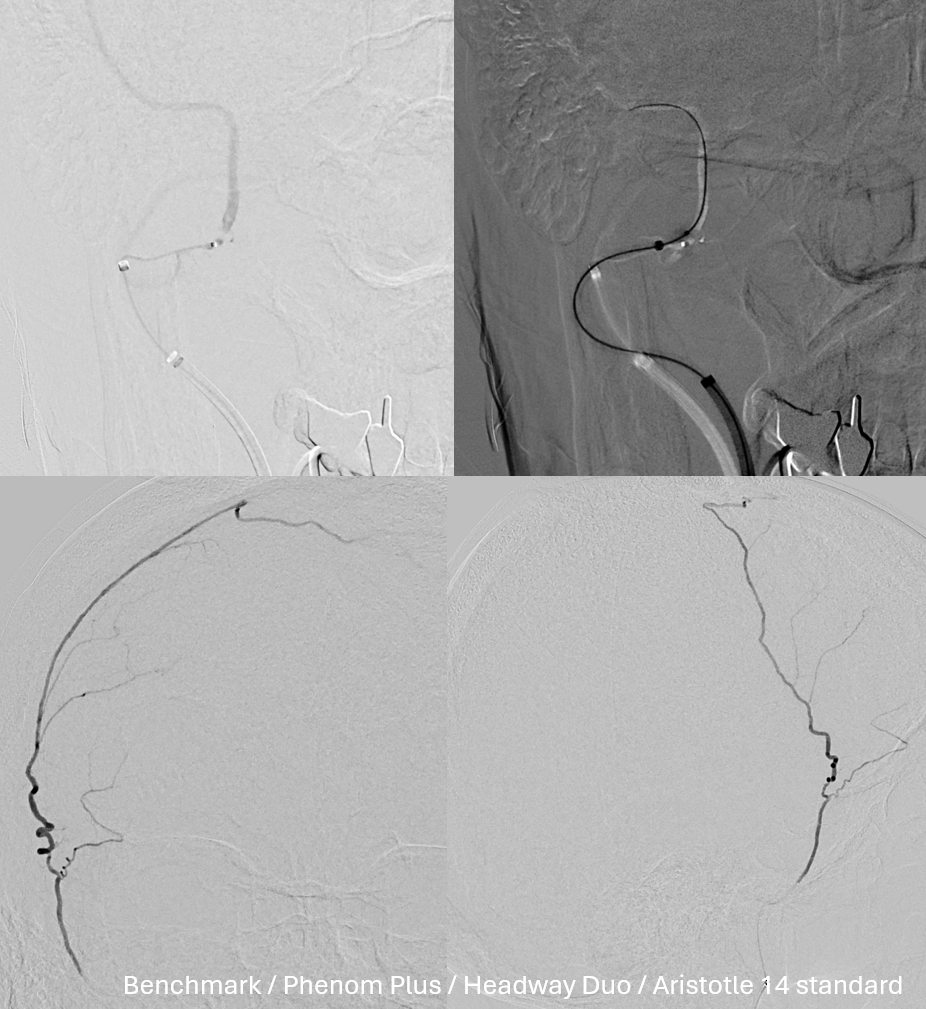

Done

The MMA remains recanalized — better than ever…